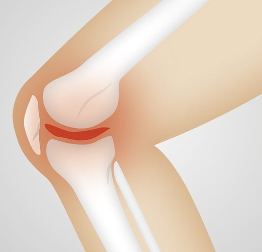

- 연골의 마모 : 무릎 관절엔 연골이 존재하며, 이 연골이 마모되면 무릎이 지지하기 위해 뼈와 뼈가 마찰되어 소리가 발생할 수 있습니다. 연골의 마모는 연령이 들어감에 따라 발생할 수 있으며, 스포츠나 부상 등으로 인해 발생할 수도 있습니다.

- 관절염 : 무릎 관절염은 무릎 관절의 연골이 파괴되거나 마모되어 뼈와 뼈가 마찰되어 소리가 발생할 수 있습니다. 무릎 관절염은 연령이 들어감에 따라 발생할 수 있으며, 과다한 체중과 부상 등이 원인이 될 수 있습니다.

무릎 연골 마모는 무릎 관절에서 연골이 손상되어 생기는 질환으로, 노화나 과도한 사용 등이 원인이 될 수 있습니다. 증상으로는 무릎 통증, 부종, 불안정성, 걷기나 등산 등 일상생활에서 무릎을 사용할 때 힘든 느낌 등이 있습니다.

무릎 연골 마모는 진행되면서 뼈와 뼈가 마주치기 때문에 더 많은 통증과 불편을 유발할 수 있습니다. 또한 연골의 기능이 손상되면 충격을 흡수하는 능력이 약해져서 무릎 관절에 더 큰 스트레스가 가해져 다른 문제가 발생할 수도 있습니다. 따라서 무릎 연골 마모는 적극적인 치료가 필요합니다.